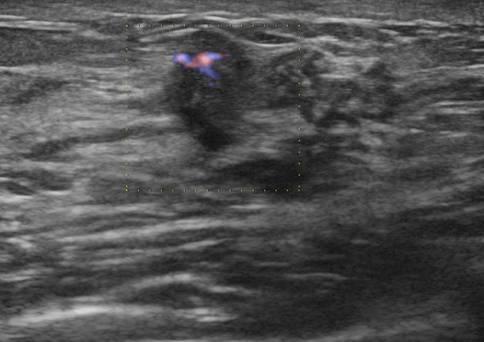

Ung thư vú

» Thông tin: Nữ giới – 25 tuổi.

» Lâm sàng: Khối tuyến vú.